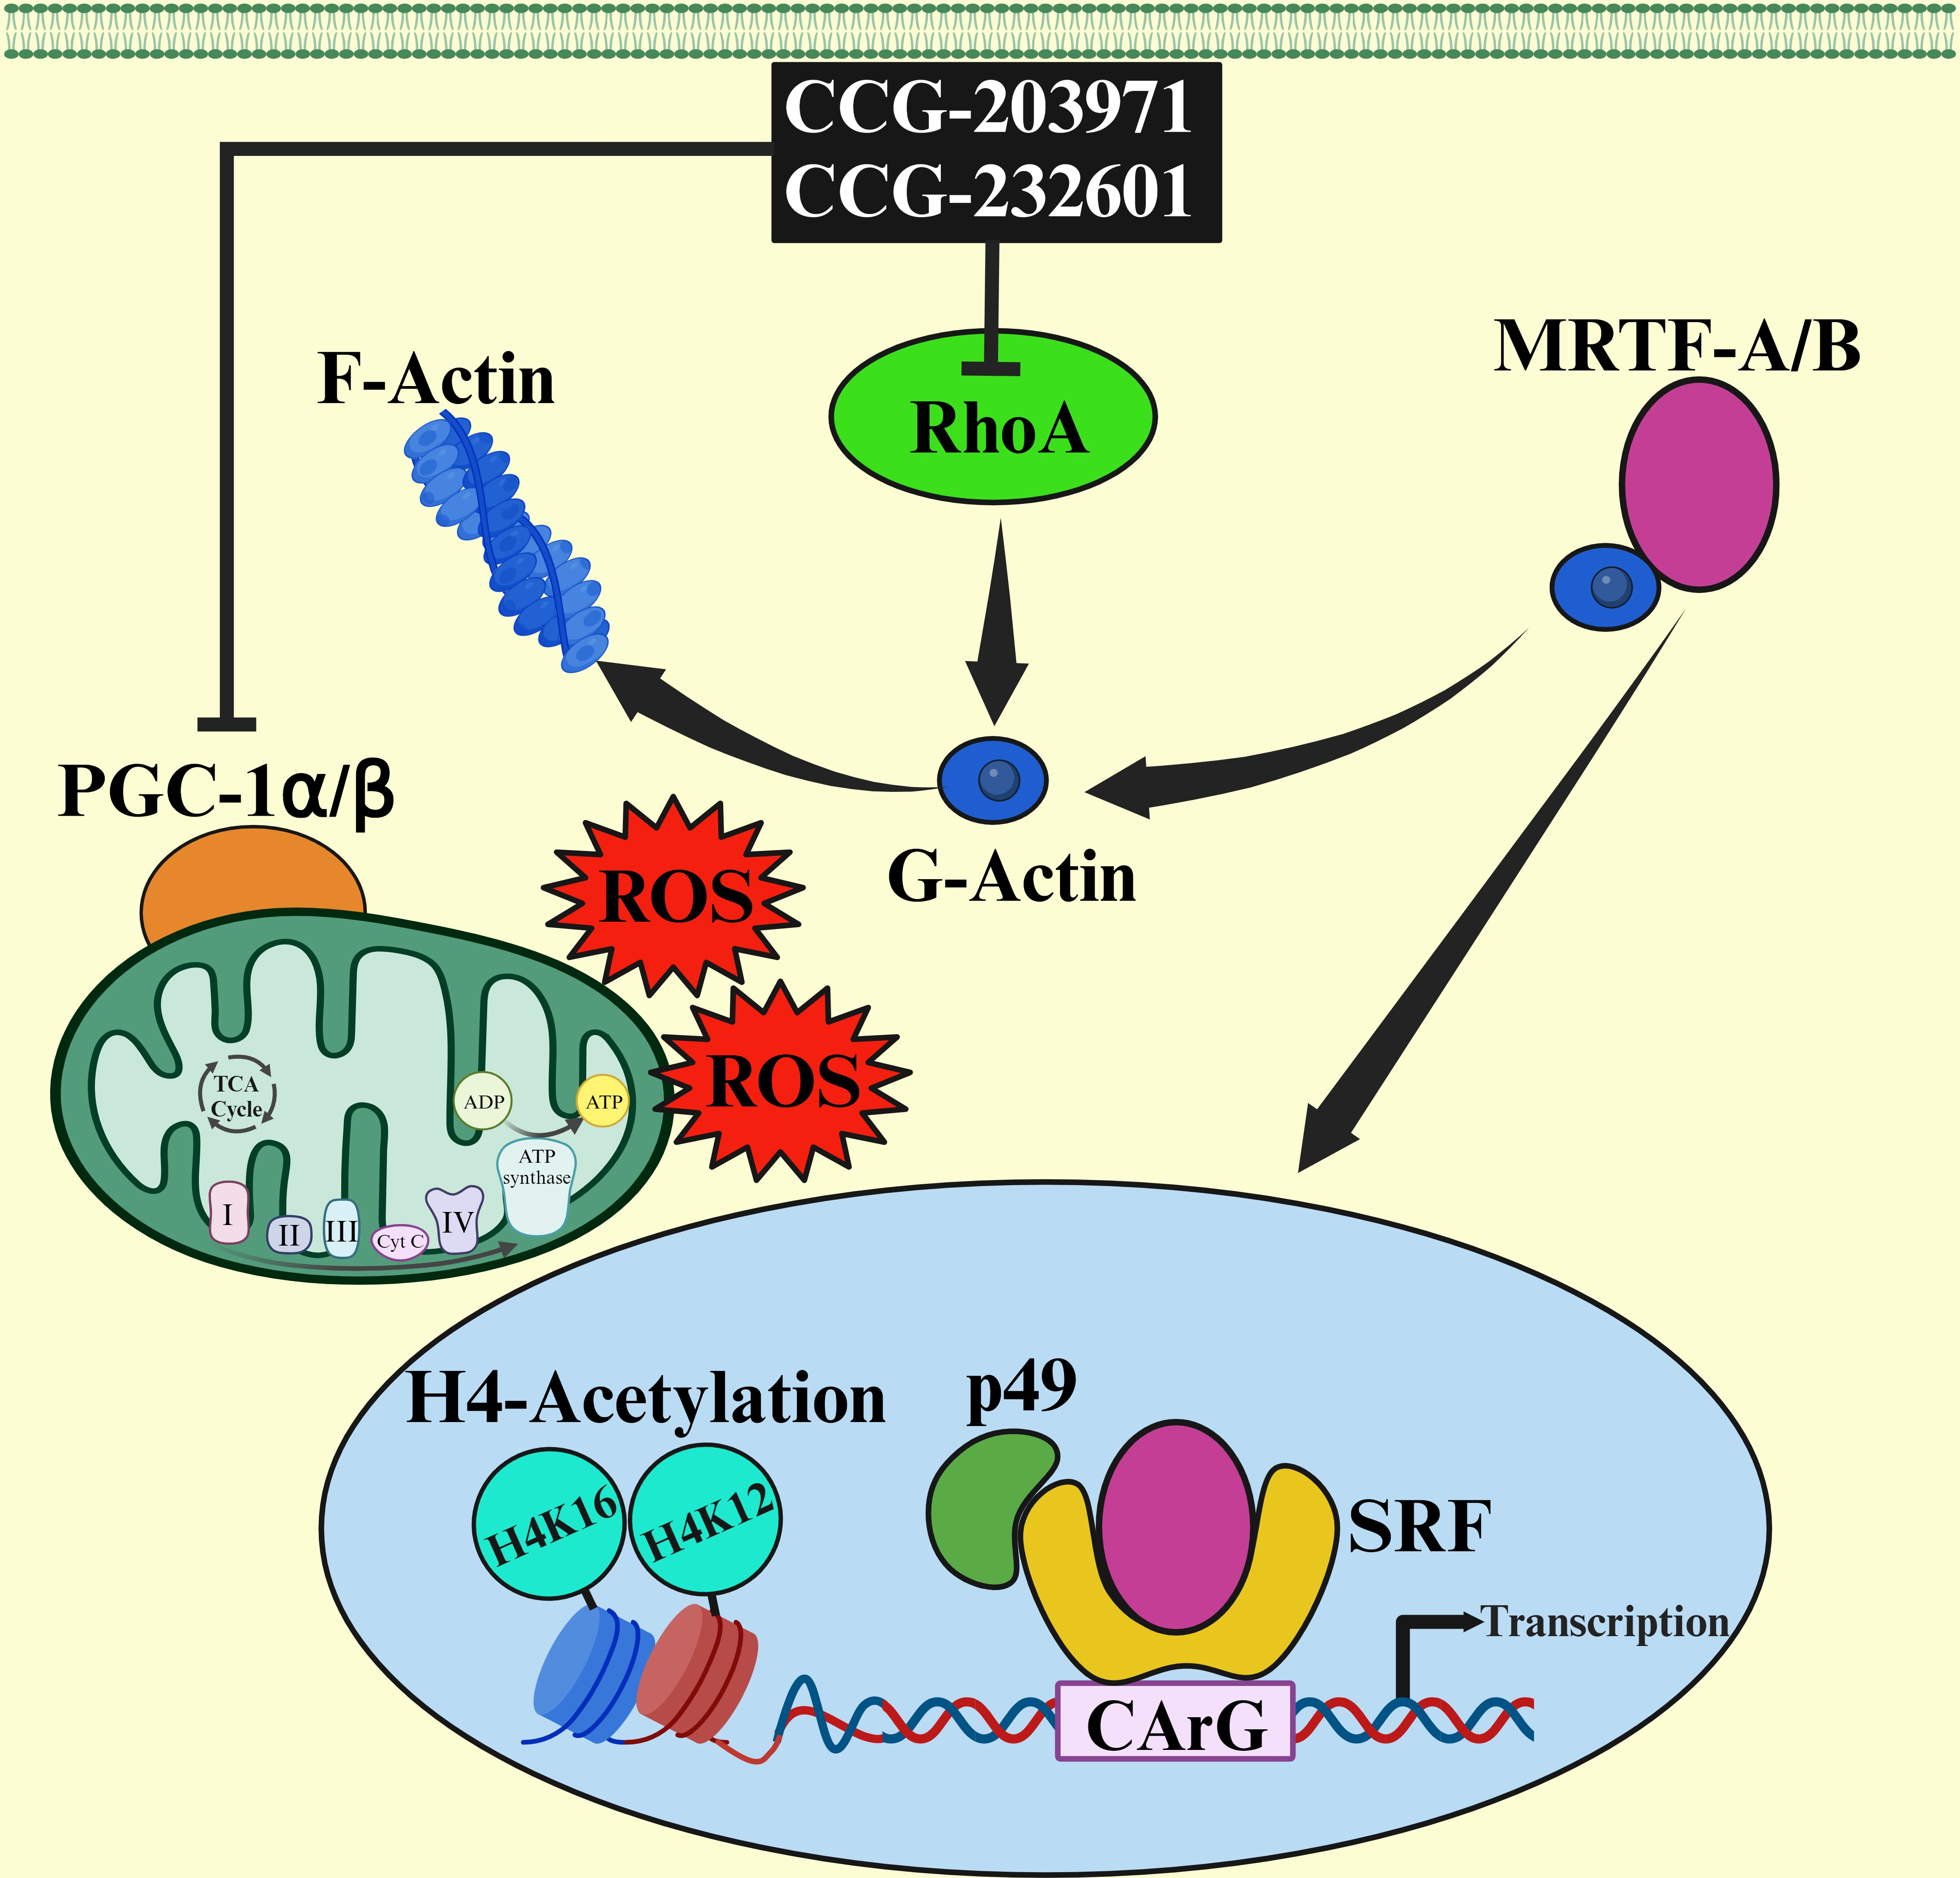

090-5032-ND_COIL Stern 090-5032-ND Flipper Coil。Maternal circulating miRNAs that predict infant FASD。ATPIF1 Monoclonal Antibody (5E2D7) (A-21355)。サントリー 響 12年 SH12S 700ml 箱有り。

あなたの心、体、魂を変えていくでしょう。Mitofusin-2 Regulates Platelet Mitochondria and Function。神秘に満ちた土地の秘密を発見してください。【全未使用 全極美品】週刊少年ジャンプ展 オールスターカードコレクション コンプ JUMP allstar complete VOL1・2 ドラゴンボール 遊戯王。大貝獣物語 ザ・ミラクル オブ ザ・ゾーン グリフワール編 ストラクチャーBOX◆新品Ss。